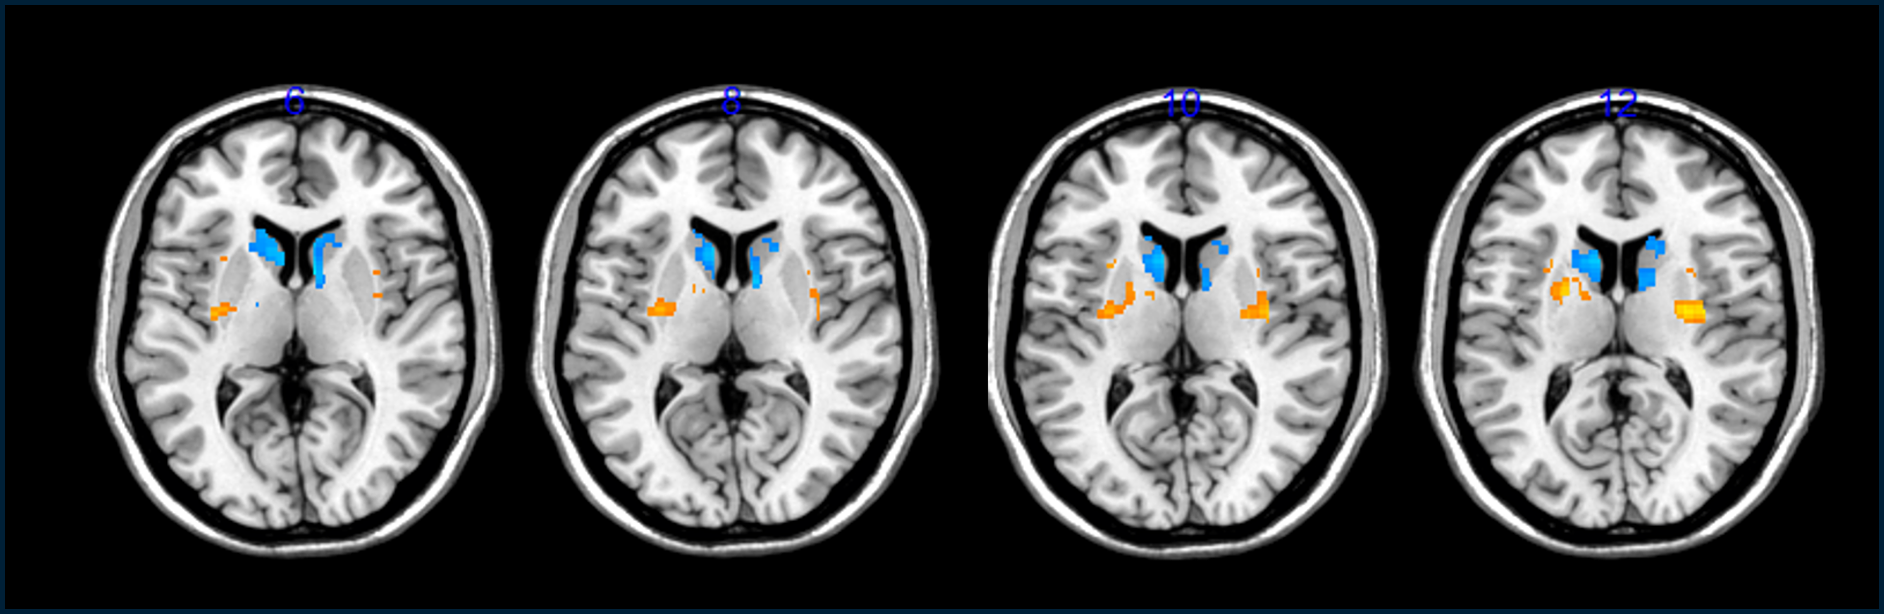

Aceste indicii că transplanturile au ajutat au provenit din scanări ale creierului care au arătat o creștere a celulelor dopaminergice în creierul pacienților, precum și o scădere a „tempului liber” sau a numărului de ore pe zi în care voluntarii s-au simțit incapacitati de simptomele lor.

Deoarece cercetătorii nu pot vedea celulele direct odată ce sunt în capul unei persoane, ei în schimb le urmăresc prezența dând oamenilor un precursor radioactiv al dopaminei și apoi urmărind absorbția acestuia în creier într-un scaner PET. Pentru Barker, aceste rezultate nu au fost atât de puternice și el spune că este „încă puțin prea devreme pentru a ști” dacă celulele transplantate au preluat și reparat creierul pacienților.